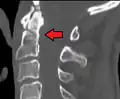

-

A fracture of the base of the dens as seen on plain X-ray -

A fracture of the base of the dens as seen on CT -